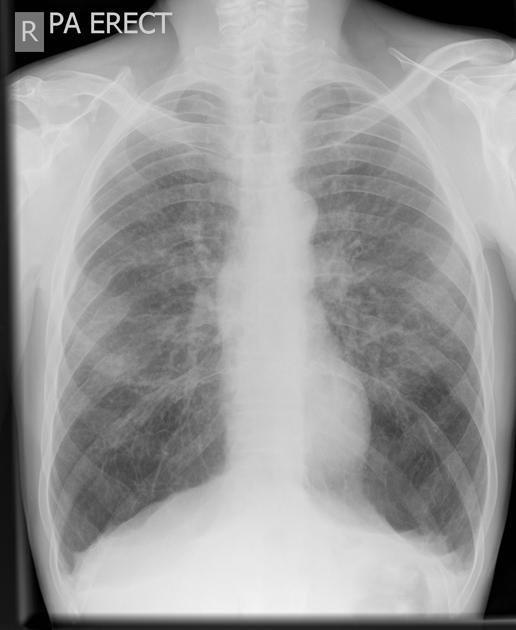

FINDINGS:

Bilateral reticulonodular shadowing with diffuse cystic changes.

Lung volumes are preserved.

No pleural abnormalities demonstrated.

Heart size is normal.

Hila and mediastinal contours are normal.

IMPRESSION:

Lymphangioleiomyomatosis

DIFFERENTIAL DIAGNOSIS:

Langerhans Cell Histiocytosis (Usually has a smoking history and present in an older age group)

Overlapping emphysematous and granulomatous disease